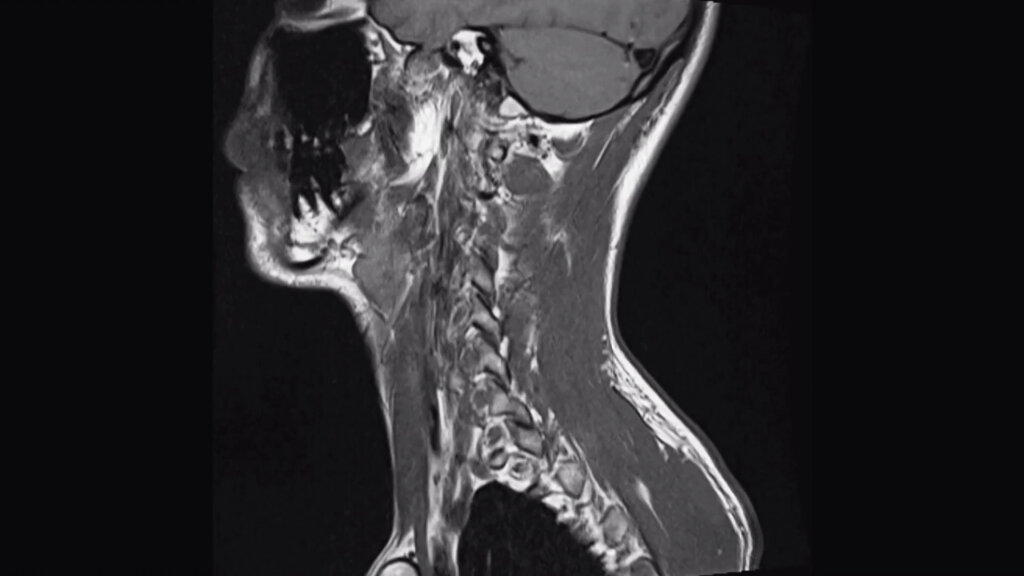

MILANO (ITALPRESS) – Negli ultimi anni si è osservato un aumento notevole dei casi di tumori all’orofaringe, che colpiscono cioè la parte centrale della gola, comprese le tonsille e la base della lingua. Solo in Italia si registrano oltre 6.000 nuovi casi ogni anno, con un aumento particolarmente significativo tra gli uomini tra i 50 e i 70 anni, e tra i giovani adulti, anche a causa di stili di vita scorretti. A livello globale, l’OMS segnala che l’incidenza di questi tumori è più alta nei paesi sviluppati, dove si stima che i tumori correlati all’infezione da HPV, il papillomavirus umano, rappresentano il 60% dei casi. Nella maggioranza dei casi, però, la prognosi è favorevole. La diagnosi precoce, insieme al continuo miglioramento delle cure e dei trattamenti chirurgici, sono gli elementi in grado di fare la differenza. Sono questi alcuni dei temi trattati da Giuseppe Mercante, professore ordinario di Otorinolaringoiatria e direttore della Scuola di specializzazione medica in Otorinolaringoiatria di Humanitas University, e referente per l’unità operativa di Otorinolaringoiatria del Gruppo Multidisciplinare Testa-Collo all’interno del Cancer Center di IRCCS Istituto Clinico Humanitas di Rozzano, intervistato da Marco Klinger, per Medicina Top, format tv dell’agenzia di stampa Italpress.